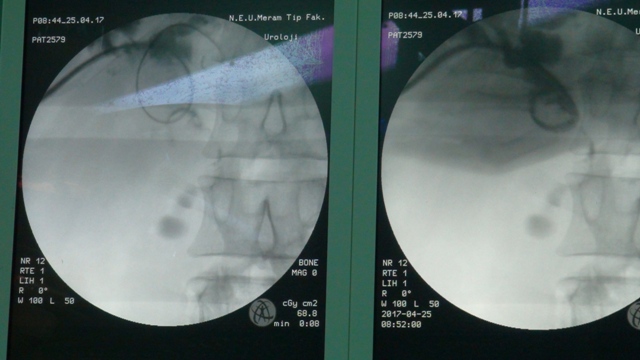

Konya'da bir hastanın karaciğerinde tespit edilen 3 santimetre çapındaki taşa, "ultra mini" denilen 2,6 milimetrelik cihazlar kullanılarak müdahale edilmesi, operasyonu gerçekleştiren doktorlara göre dünyada ilk oldu

Konya'da bir hastanın büyük olduğu için normalde işlem yapılamayan karaciğer taşına, 2,6 milimetrelik ultra mini cihazlarla müdahale edilmesi, operasyonu gerçekleştiren doktorlara göre dünya tıp literatüründe ilk oldu.

"Karaciğer çok kanamalı bir organ. Kanallar küçük. Buradaki işlemler tahribata neden olabilir. Bizim kullandığımız aletlerle kanallarda rahat hareket edip, taşa ulaştık. Kanama ihtimalini en az düzeye indirdik. Ameliyattan sonra açılan delik daha çabuk kapandı. 'Ultra mini' diyebileceğimiz yaklaşık 2,6 (8F) milimetrelik aletleri kullanarak müdahaleyi yaptık. Yurt dışında daha kalın, yaklaşık 1 santimetreye yakın aletlerle yapılmış ender uygulamalar var. Biz ultra mini dediğimiz aletlerle bu işi dünyada ilk yapan klinik olmanın gururunu yaşıyoruz. Şu anda ameliyat görüntülerini hazırlıyoruz. Uluslararası camiaya bunu duyuracağız. Video sunumlarla uluslararası toplantılarda uygulamayı anlatacağız. Endoskopik taş tedavisi tecrübemizi karaciğerdeki taşa uyguladık. Sonuçta hastamızın da bizim de yüzümüz güldü. Hepimiz mutluyuz."